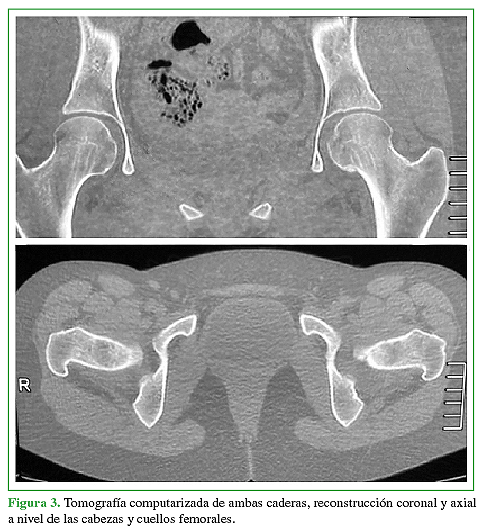

Acceso mediante suscripción PDF Acceso mediante suscripción PDF_EN (English) Acceso mediante suscripción Figura 1 Acceso mediante suscripción Figura 2 Acceso mediante suscripción Figura 3 Acceso mediante suscripción Figura 4 Acceso mediante suscripción Figura 5 Acceso mediante suscripción Figura 6 Acceso mediante suscripción HTML